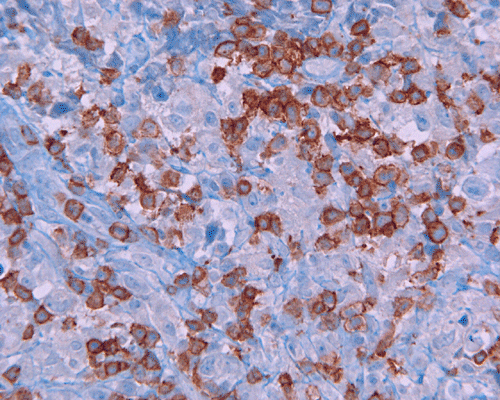

Paraffin sections: The entire volume of the tissue is made up of a granulomatous inflammation with poorly formed granuloma (Panel F, G, and H). The density of the lymphocytes is variable in different areas. In some areas, there is a rather intense lymphocytic infiltration accompanied by scant atypical cells with enlarged nulcei and prominent nucleoli (arrows in Panel I and J, Panel J is a higher magnification of Panel I). These atypical cells are quite easy to be missed. No microorganisms were identified by acid fast stain, PAS stain or GMS stain. The lymphocytes but not the atypical cells are positive for CD20 (Panel K) or CD3 (Panel L). The granulomatous background is strongly positive for CD68 (Panel M). Only rather faint positive staining for placental alkaline phosphatase (PLAP) is demonstrated and the interpretation is difficult as they are present in areas with crush artifact (Panel N). Many of the large, atypical cells are positive for CD117 (c-kit) (Panel O).

Immunohistochemically, the neoplastic cells show cytoplasmic membranous patten, sometimes diffuse cytoplasmic pattern, of staining for placental alkaline phosphatase (PLAP). Detection of c-kit (CD 117) in germinoma has been demonstrated and serves as a good diagnostic aid. Activating KIT mutations may contribute to tumorigenesis in germinoma 6, 7, 8. Syncytiotrophoblastic cells can be positive for human chorionic gonadotrophin (hCG). Occasional positive immunoreactivity for cytokeratin has been described and should not be taken as the sole evidence for embryonal carcinoma.